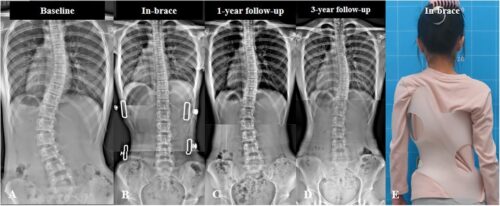

حزام اعوجاج العمود الفقري: يُستخدم إذا تجاوز الانحناء 20 درجة وكان الطفل لا يزال في مرحلة النمو. يساعد الحزام على تقليل اعوجاج العمود الفقري في وضع صحيح ويمنع زيادة الانحناء.